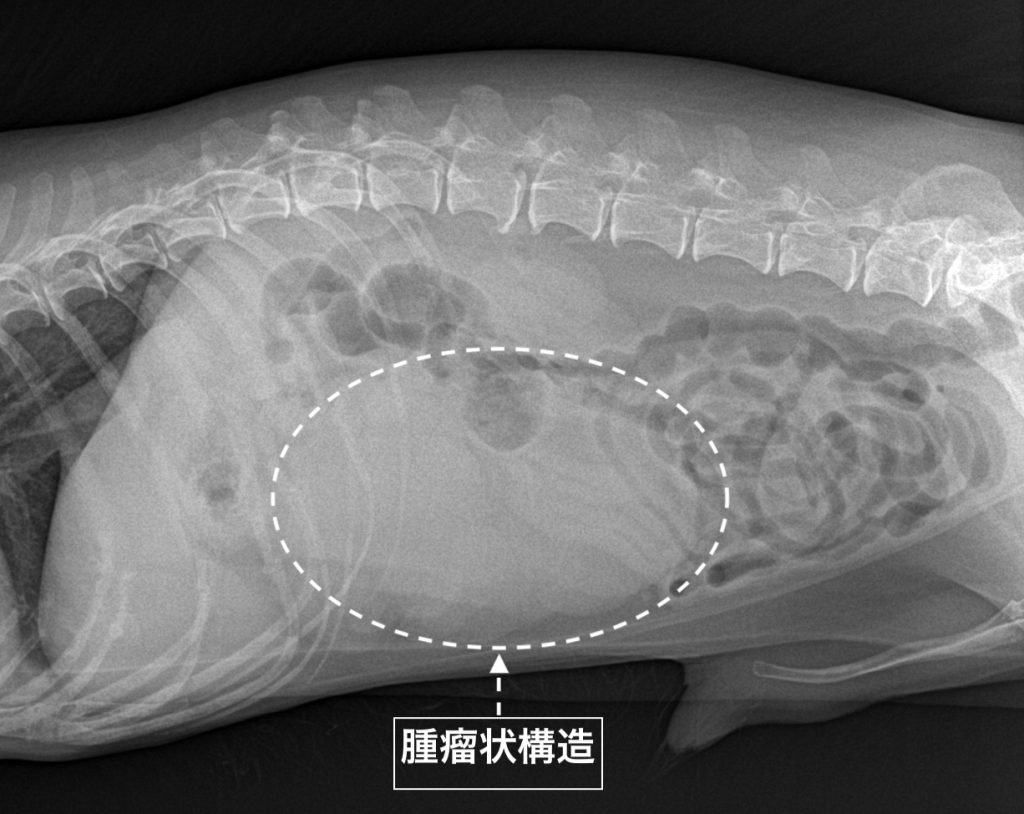

レントゲン検査

上腹部腹腔内正中に腫瘤状構造が認められました。

実際のレントゲン画像です。腹腔内正中に充実性の腫瘤上構造が確認できます。